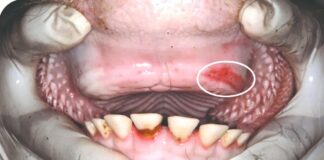

Stomatitis kod goveda – usporava žvakanje i probavu

Stomatitis je upala usne šupljine i sluznice usta kod goveda različitog stupnja i oblika. Osim same usne šupljine upalne promjene mogu zahvatiti i dublje...